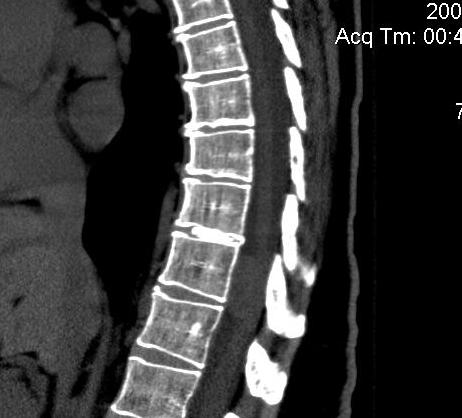

Xray

Disc space narrowing / degenerative changes

> 50% thoracic discs associated with calcified disc material in canal

- probably indicates chronicity

MRI

Very sensitive

- 40% incidence asymptomatic thoracic disc protrusion